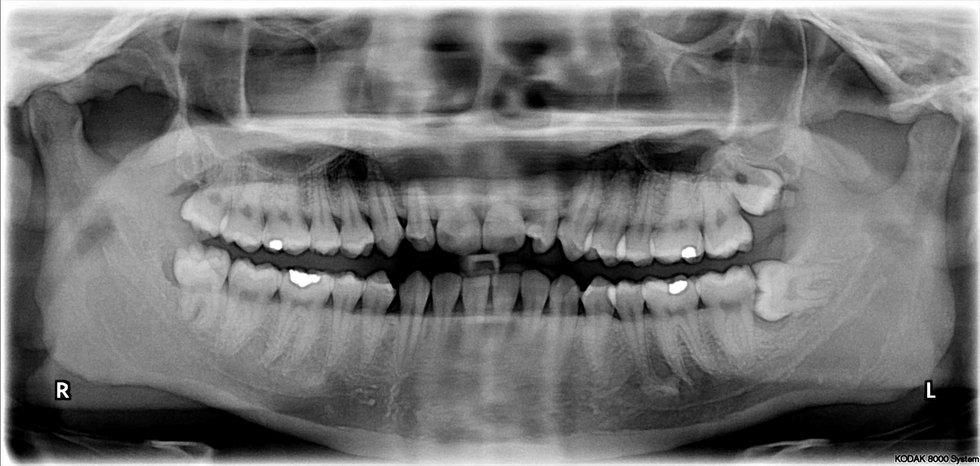

The 15 Stages Of Getting Your Wisdom Teeth Removed

Pain, Blood, and Hunger, Oh My!

I just got my wisdom teeth out 5 days ago, and it was a roller coaster. I was terrified when I first went into the dentist's office. What if I woke up during surgery? What if he butchers my mouth? Little did I know that I should not have feared what would happen during surgery; rather, I should have worried about what life would be like after surgery. If you are reading this and about to get your wisdom teeth removed, do not fret. It is not as bad as people make it out to be. It is just a lot of difficultly and first world problems. Here are 15 "stages" of complaints and thoughts that I had when I was healing from my wisdom teeth surgery.